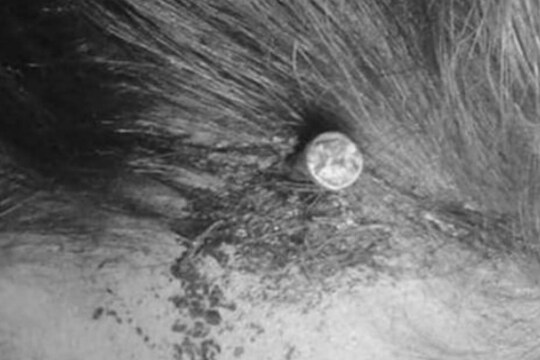

नवी दिल्ली 12 फेब्रुवारी : पाकिस्तानमधून एक अतिशय हैराण करणारं प्रकरण समोर आलं आहे (Pakistan Shocking News). यात एका गर्भवती महिलेच्या डोक्यात दोन इंच लांब खिळा ठोकण्यात आला (Nail Hammered into Head of Pregnant Woman). सुदैवाने हा खिळा तिच्या डोक्यात खोल शिरला नाही आणि तिचा मृत्यू झाला नाही. Metro च्या वृत्तानुसार, पाकिस्तानी अधिकाऱ्यांसमोर एक अजब प्रकरण आलं, जेव्हा डॉक्टरांनी त्यांना सांगितलं की महिलेच्या डोक्यात खिळा अडकलेला आहे. 49 वर्षांच्या खासदाराचं 18 वर्षांच्या तरुणीसोबत तिसरं लग्न, मुलीला होतोय संताप डॉक्टर हैदर खान यांनी सांगितलं की आधी महिलेनं स्वतः हा खिळा डोक्यातून काढण्याचा प्रयत्न केला. मात्र, खिळा न निघाल्याने ती पेशावरच्या उत्तर-पश्चिमी शहरातील एका रुग्णालयात गेली. त्यावेळी ती पूर्णपणे शुद्धीवर होती मात्र अतिशय वेदनेत होती. जेव्हा तिच्या डोक्याचा एक्स-रे केला गेला तेव्हा त्यात दोन इंचाच खिळा दिसला. सुदैवाने हा खिळा डोक्यामध्ये खोलवर शिरला नव्हता, अन्यथा महिलेला आपला जीव गमवावा लागला असता. महिलेनं सुरुवातीला रुग्णालयातील कर्मचाऱ्यांना सांगितलं होतं की कोणाच्यातरी सल्लावरुन तिने स्वतः आपल्या डोक्यात खिळा ठोकून घेतला. मात्र, नंतर तिने सांगितलं की हे काम दुसऱ्याच व्यक्तीने केलं आहे. पेशावर पोलीस महिलेच्या डोक्यात खिळा ठोकणाऱ्याचा शोध घेत आहेत. पाकिस्तानमध्ये जवळच्या नातेवाईंकामध्ये लग्न करण्याने या आजाराचा वाढला धोका! या महिलेला तीन मुली आहेत आणि चौथ्यांदाही तिच्या गर्भात मुलगीच होती. त्यामुळे ती एका फॅथ हिलरच्या संपर्कात आली, यावेळी त्याने मुलगाच होणार याची खात्री देत महिलेच्या डोक्यात खिळा ठोकला. या खिळ्यामुळे महिलेच्या माथ्याच्या वरच्या भागात खड्डा झाला होता. मात्र, सुदैवाने डोक्यात हा खिळा आतपर्यंत गेला नाही. डॉक्टरांनी सांगितलं की खिळा आतमध्ये घुसवण्यासाठी हातोडीचा किंवा इतर जड वस्तूचा वापर केला गेला आहे.